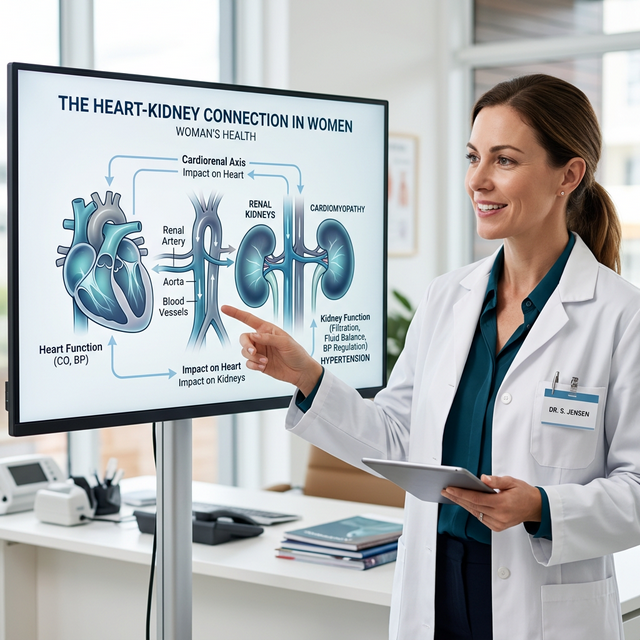

O alerta de especialistas destaca que a hipertensão é a segunda maior causa de diálise no Brasil e o risco vai além do coração.

Entenda por que a pressão alta é a segunda maior causa de diálise e como a dieta DASH pode ajudar.

Estudos alertam para o aumento dos riscos cardiovasculares no público feminino e conexão com rins.